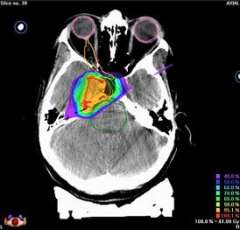

CT image showing pear-shaped tumor

Conformal radiation dose delivery with Novalis. This CT image shows the how this pear-shaped tumor, outlined with a thin red line, can be evenly dosed with the appropriate amount of radiation (in the 90th percentile of the prescribed dose, or the yellow area) in a manner that matches the shape of the tumor. A similar treatment plan would not be possible with Gamma Knife.